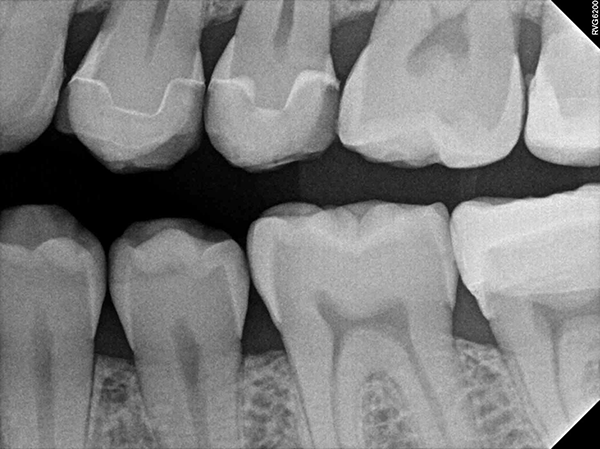

Visual examination revealed decay on the mesial marginal ridge and distal marginal ridge of tooth #13 as well as extensive buccal and occlusal decay on tooth #15 (Figs. 1-2). Bitewing radiographs and intraoral photographs were taken, which confirmed the above diagnosis and also exposed additional decay on the distal of tooth #12 (Figs. 3-4).

Fig. 3 Fig. 4

Once the milling was complete, the restorations were polished, the fit was verified and they were cemented in place (Fig. 12). Final control radiographs were acquired with the RVG 6200 intraoral sensor to confirm the fit of the inlays and crown (Figs. 13-14).

Fig. 13 Fig. 14